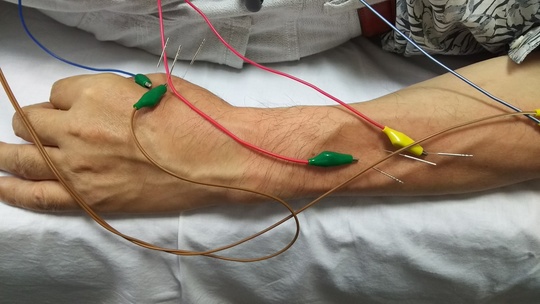

左拇指外転、伸展マヒ 62歳男性

頸椎5/6に変形著しく、担当医に手術を勧められるも「切りたくない」という患者希望があり、リハビリテーションを行っていた。

「ボタンがつけられない。手を開けない」との訴えで、病院以外に鍼治療を希望され、継続治療中。

拇指伸展筋、拇指外転筋、合谷―孔最への鍼通電に加えて、アイシングならびに皮膚刺激による末梢から中枢への物理刺激で改善を行っている。